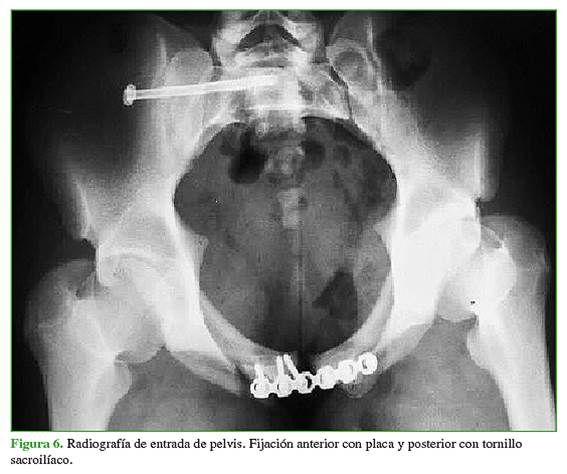

Los tipos de fijación analizados se dividieron en dos grupos. El primer grupo incluyó a los pacientes operados con fijación anterior con placa mediante un abordaje de Pfannenstiel y percutáneo sacroilíaco. Al segundo grupo lo conformaron los pacientes operados únicamente con fijación anterior con placa por medio de un abordaje tipo Pfannenstiel (sin fijación posterior), más los operados con fijación externa anterior y percutánea sacroilíaca. La división en grupos se realizó de esa manera para comparar el tratamiento más aceptado en la actualidad y recomendado en la bibliografía (fijación anterior con placa y posterior percutánea), con el resto de los tratamientos realizados. El tratamiento para cada paciente se seleccionó según las características de cada uno de ellos, sus enfermedades y lesiones asociadas, y en conjunto con los demás servicios tratantes. Además, los primeros pacientes de la serie habían sido tratados solo con fijación anterior, en los últimos años de la serie, se agregó la fijación posterior percutánea. La fijación anterior se realizó, en todos los casos, con una placa de reconstrucción o una placa DCP de 3,5 mm, según la disponibilidad. La mayoría de los pacientes fueron operados con placas de reconstrucción de 3,5 mm y dos, con placas DCP 3,5 mm. Los tornillos sacroilíacos utilizados fueron de 6,5 mm y 7 mm.

A cinco pacientes (21,73%) se les realizó únicamente fijación anterior con un abordaje tipo Pfannenstiel, 13 (56,52%) fueron operados mediante fijación anterior y percutánea sacroilíaca (Figuras 5-7) y cinco (21,73%), mediante fijación externa anterior y percutánea sacroilíaca. La reducción posoperatoria fue <1 cm en 16 pacientes (69,57%). Cinco (21,73%) sufrieron una infección del sitio quirúrgico.